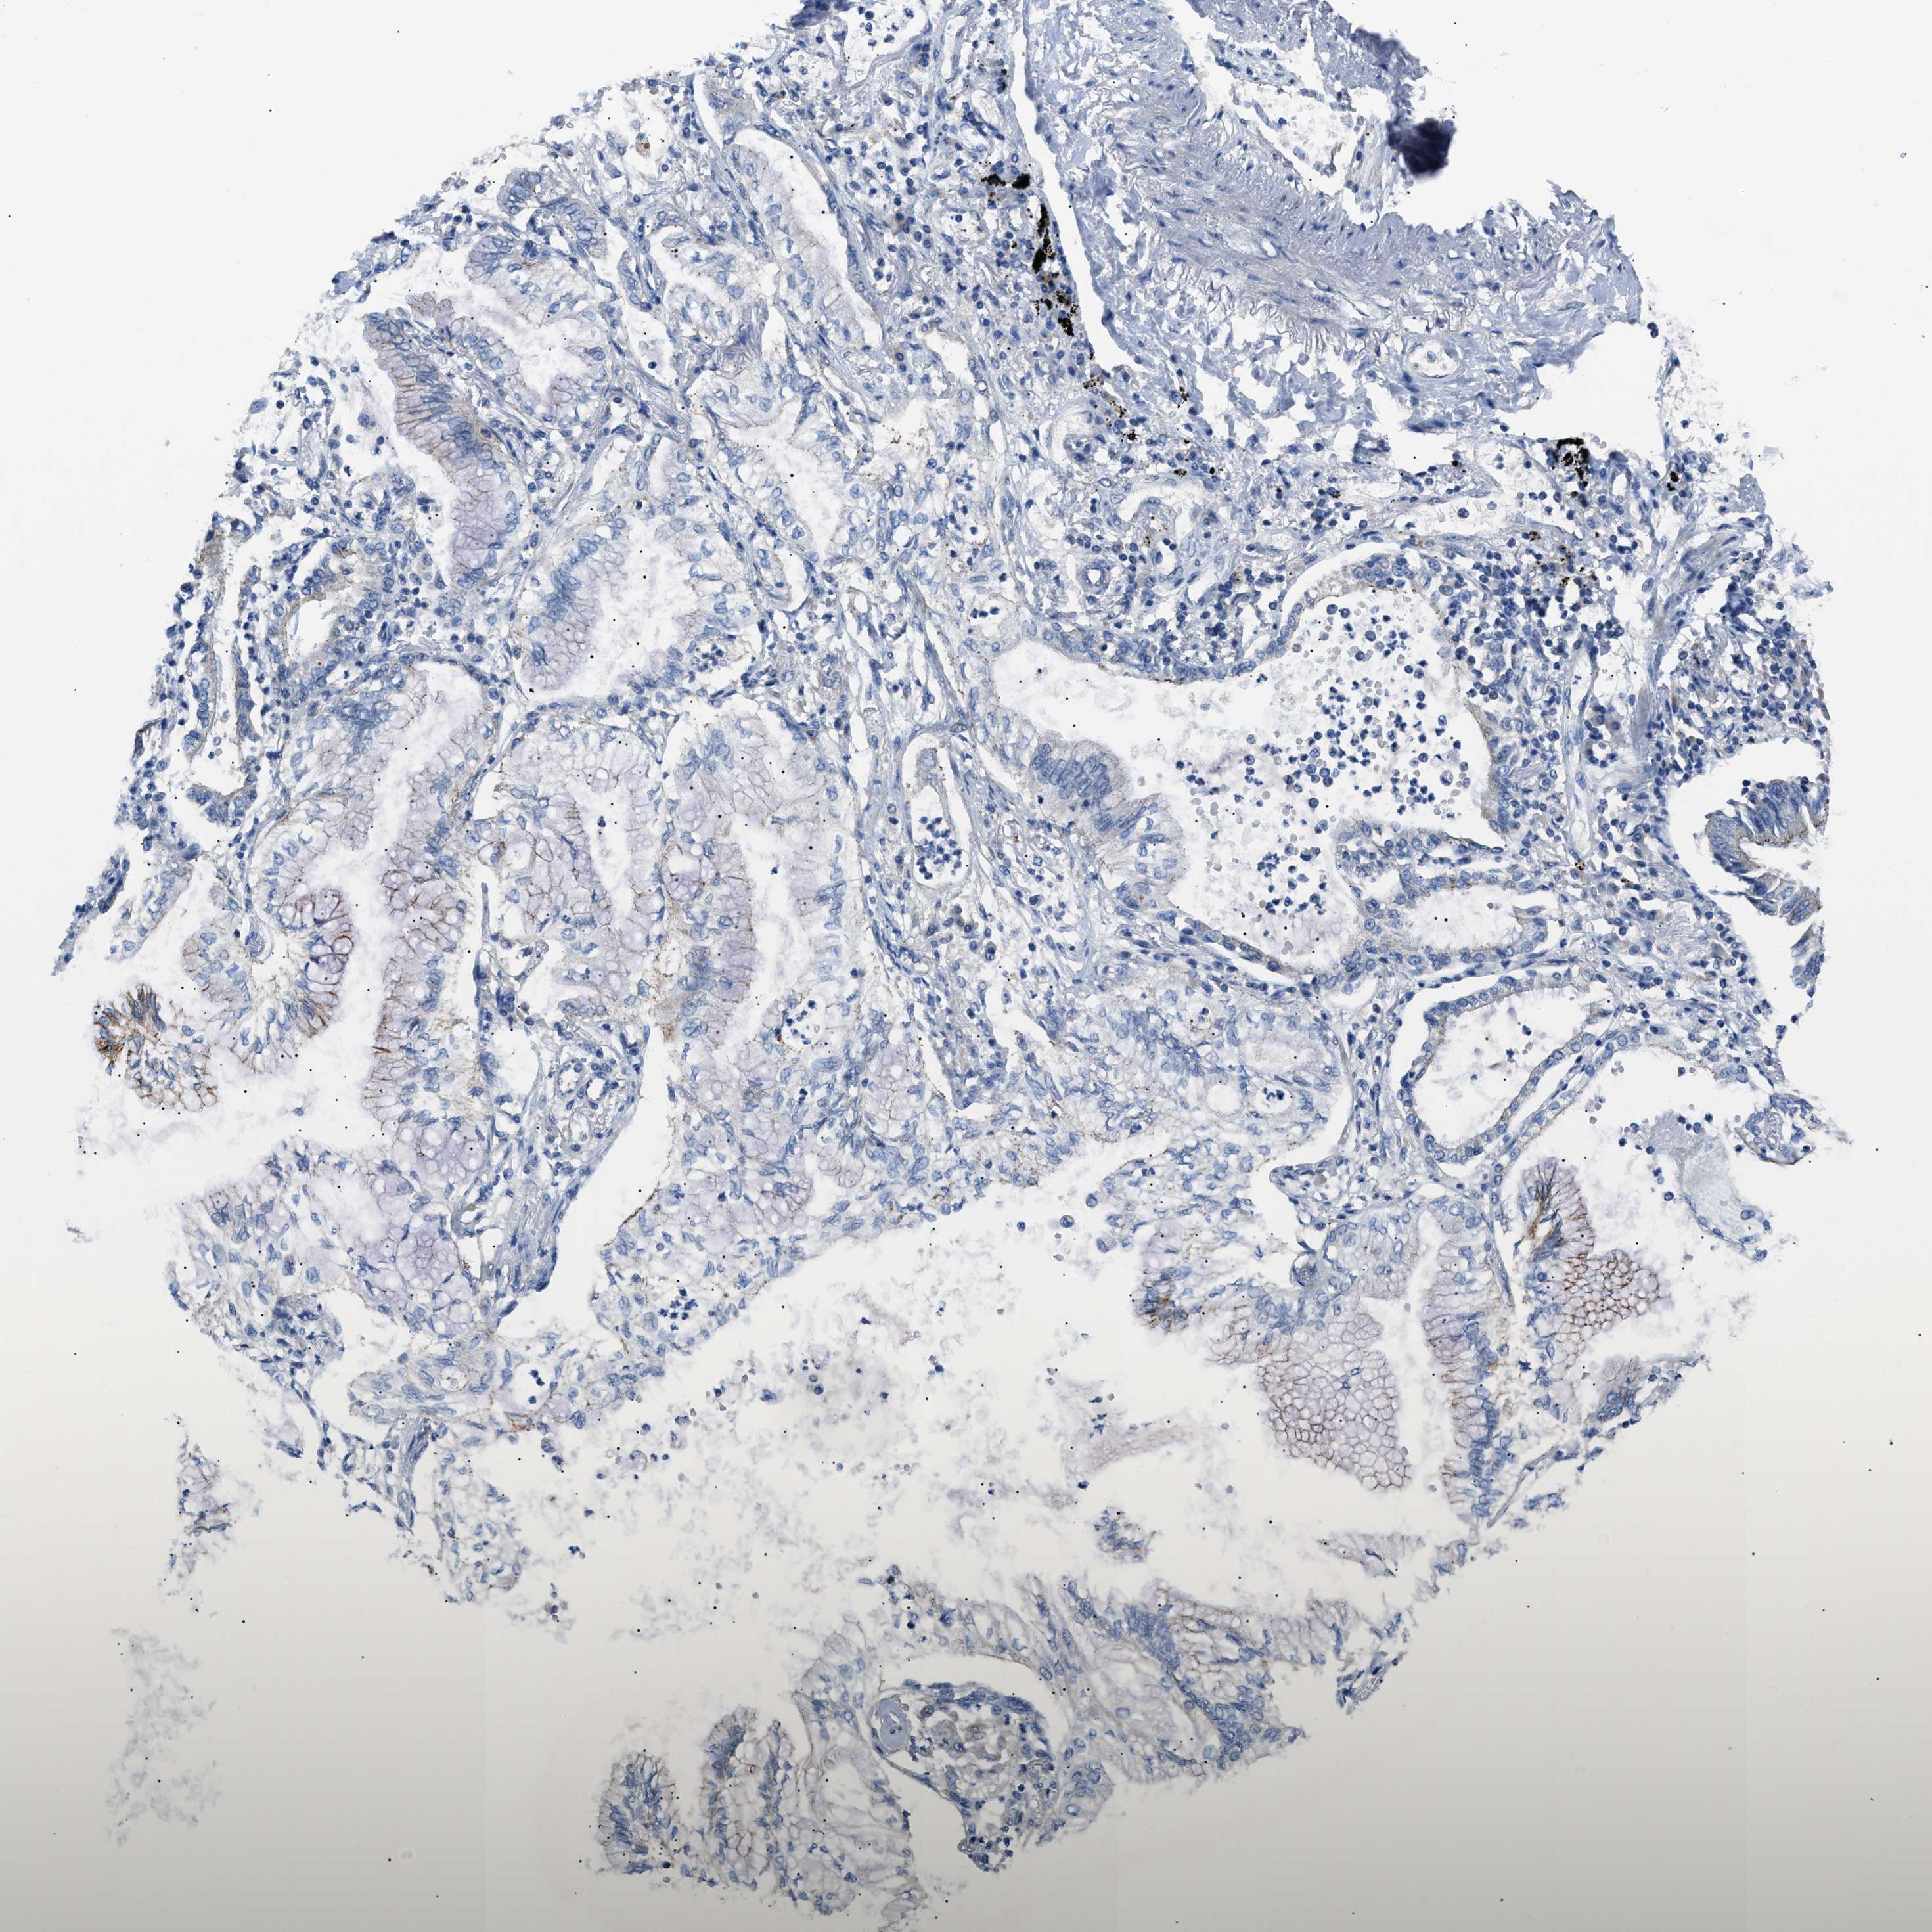

CANCER LUNG CANCER Show tissue menu

Lung cancer

Human cancer

Lung adenocarcinoma

Lung squamous cell carcinoma